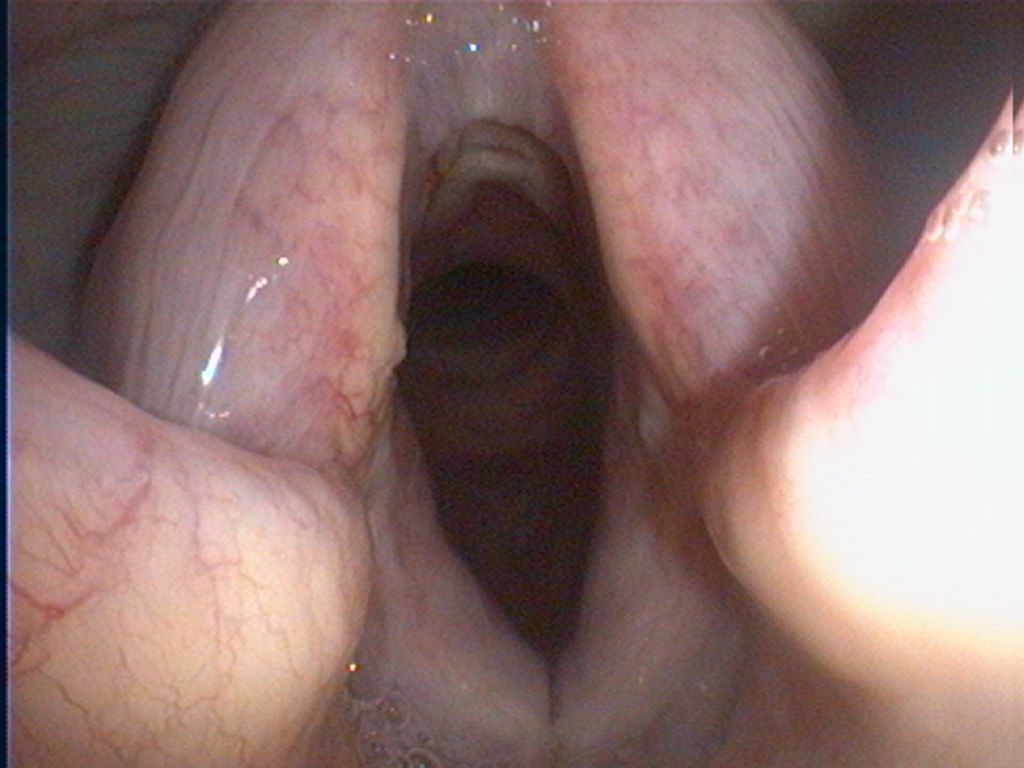

Endoscopie laryngée

L’exploration endoscopique du larynx constitue une indication spécifique, notamment chez les chiens présentant des troubles respiratoires inspiratoires, des modifications de la voix ou des épisodes de détresse respiratoire. Elle permet d’évaluer la mobilité des cartilages aryténoïdes, de diagnostiquer une paralysie laryngée, de visualiser des lésions inflammatoires, traumatiques ou tumorales, et d’adapter au mieux la stratégie thérapeutique.

Stridor sur paralysie laryngée.

Cette vidéo illustre un stridor marqué chez un chien atteint de paralysie laryngée. Le stridor correspond à un bruit respiratoire anormal, aigu et souvent impressionnant, audible principalement à l’inspiration. Il est provoqué par un rétrécissement des voies respiratoires supérieures, qui entraîne une accélération turbulente de l’air lors de son passage.

Dans le cas présenté, le stridor est lié à une paralysie laryngée. Normalement, lors de l’inspiration, les cartilages aryténoïdes du larynx s’écartent activement afin d’ouvrir la filière respiratoire et de permettre un passage d’air fluide vers la trachée. En situation de paralysie laryngée, ces cartilages ne s’ouvrent plus correctement, voire restent en position quasi fermée. L’air inspiré doit alors passer à travers une ouverture trop étroite, ce qui génère un bruit caractéristique, souvent comparé à un sifflement ou à un ronflement aigu.

Le stridor est généralement plus marqué à l’effort, lors de l’excitation ou par temps chaud, car les besoins ventilatoires augmentent et aggravent la gêne respiratoire. Il peut s’accompagner de dyspnée, d’intolérance à l’effort, de cyanose, voire de détresse respiratoire aiguë dans les formes sévères. Chez certains animaux, des épisodes de collapsus ou de malaise peuvent survenir.

La paralysie laryngée est le plus souvent d’origine neurologique, liée à une atteinte du nerf laryngé récurrent, et peut être idiopathique, notamment chez le chien âgé, ou associée à des affections plus générales du système nerveux périphérique. L’examen endoscopique du larynx est l’examen de référence pour confirmer le diagnostic, en visualisant directement l’absence ou l’insuffisance de mobilité des cartilages aryténoïdes.

Le stridor constitue donc un signe clinique d’alerte important. Sa reconnaissance permet d’orienter rapidement vers une exploration des voies respiratoires supérieures et d’adapter la prise en charge, qu’elle soit médicale ou chirurgicale, afin de prévenir les complications respiratoires potentiellement graves.